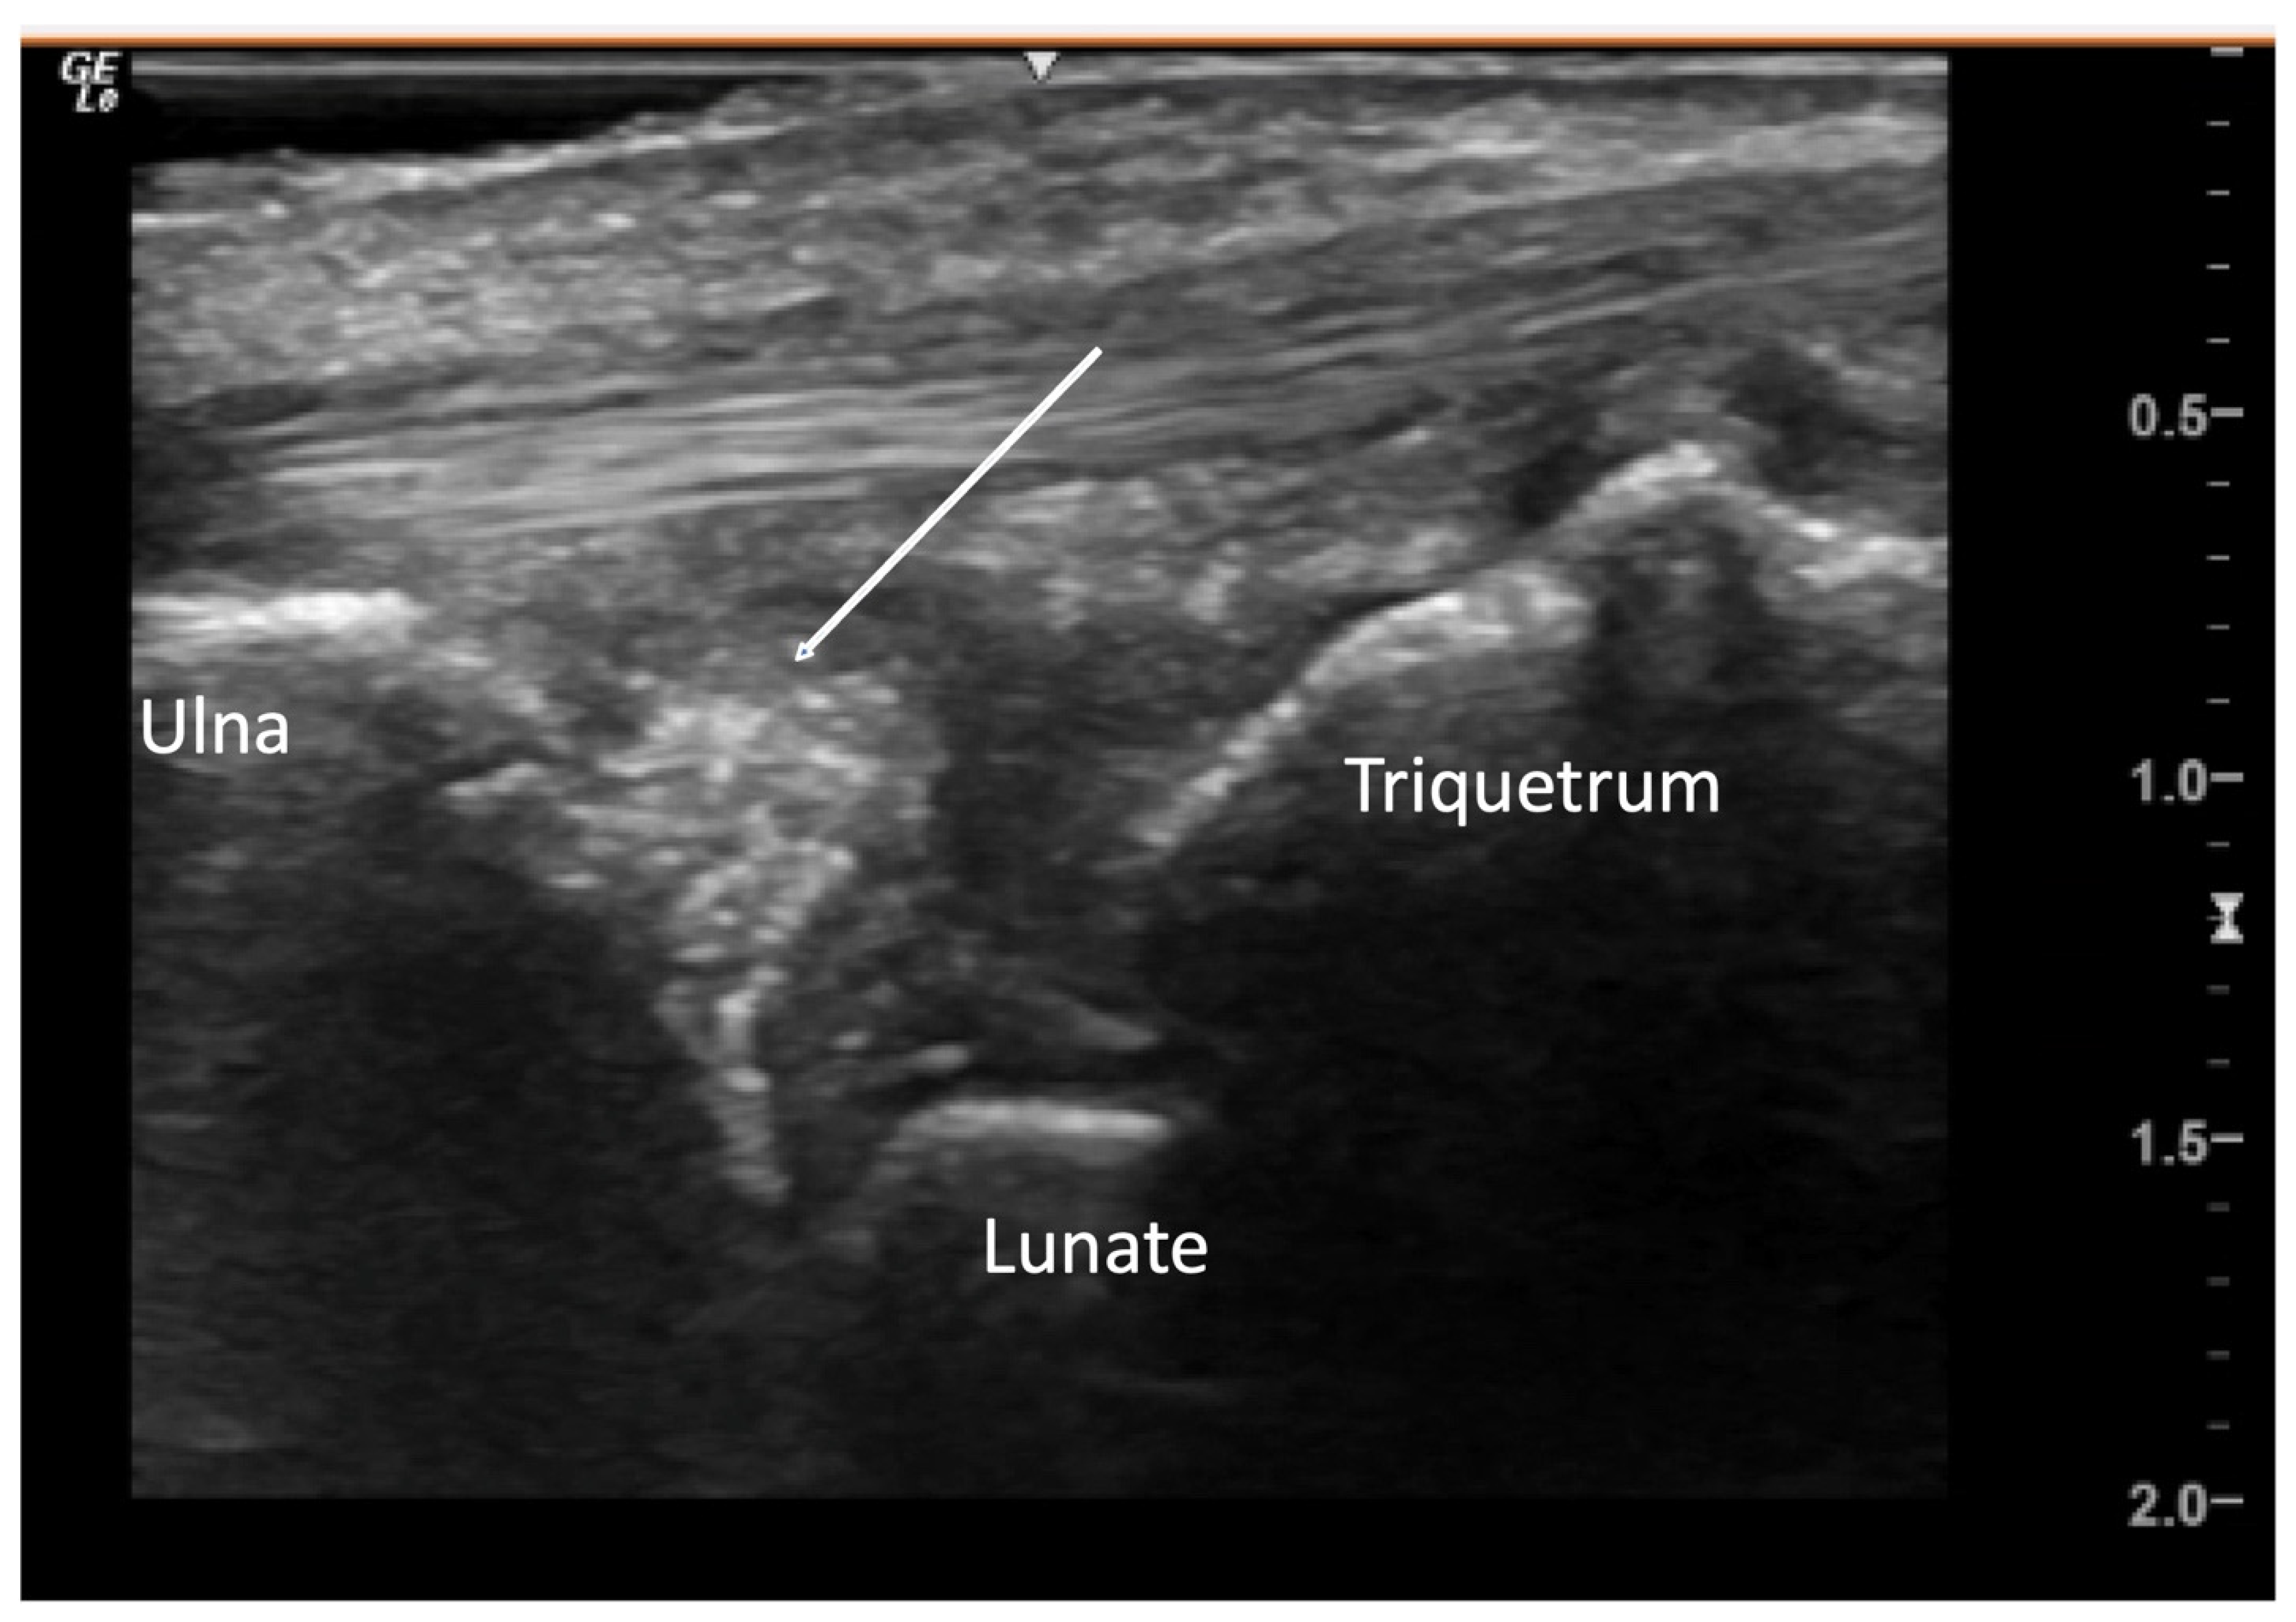

4.2.3. Ulnar Aspect